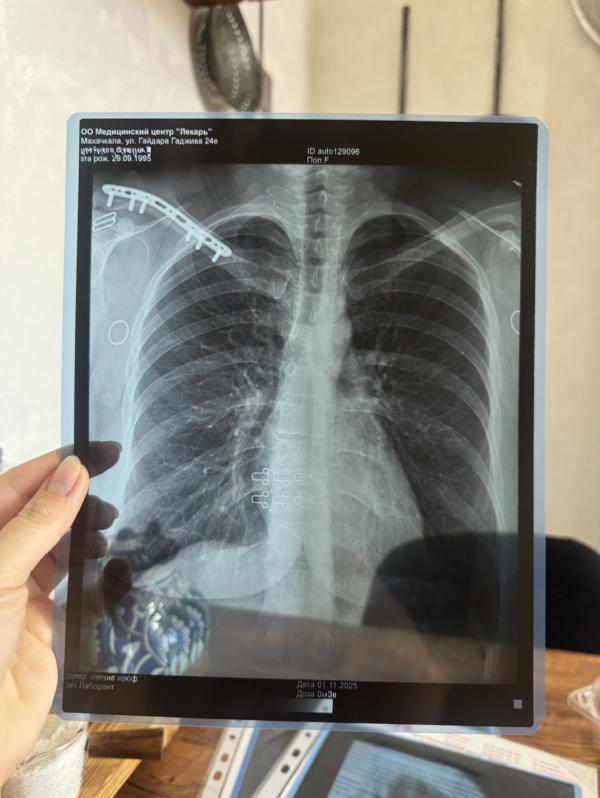

Пневмония перед установкой брекетов: что делать и как быть

Да здравствует пневмония за 4 дня до установки брекетов.

🥲+ сколиоз

Радует только то, что ключица зажила…🥹